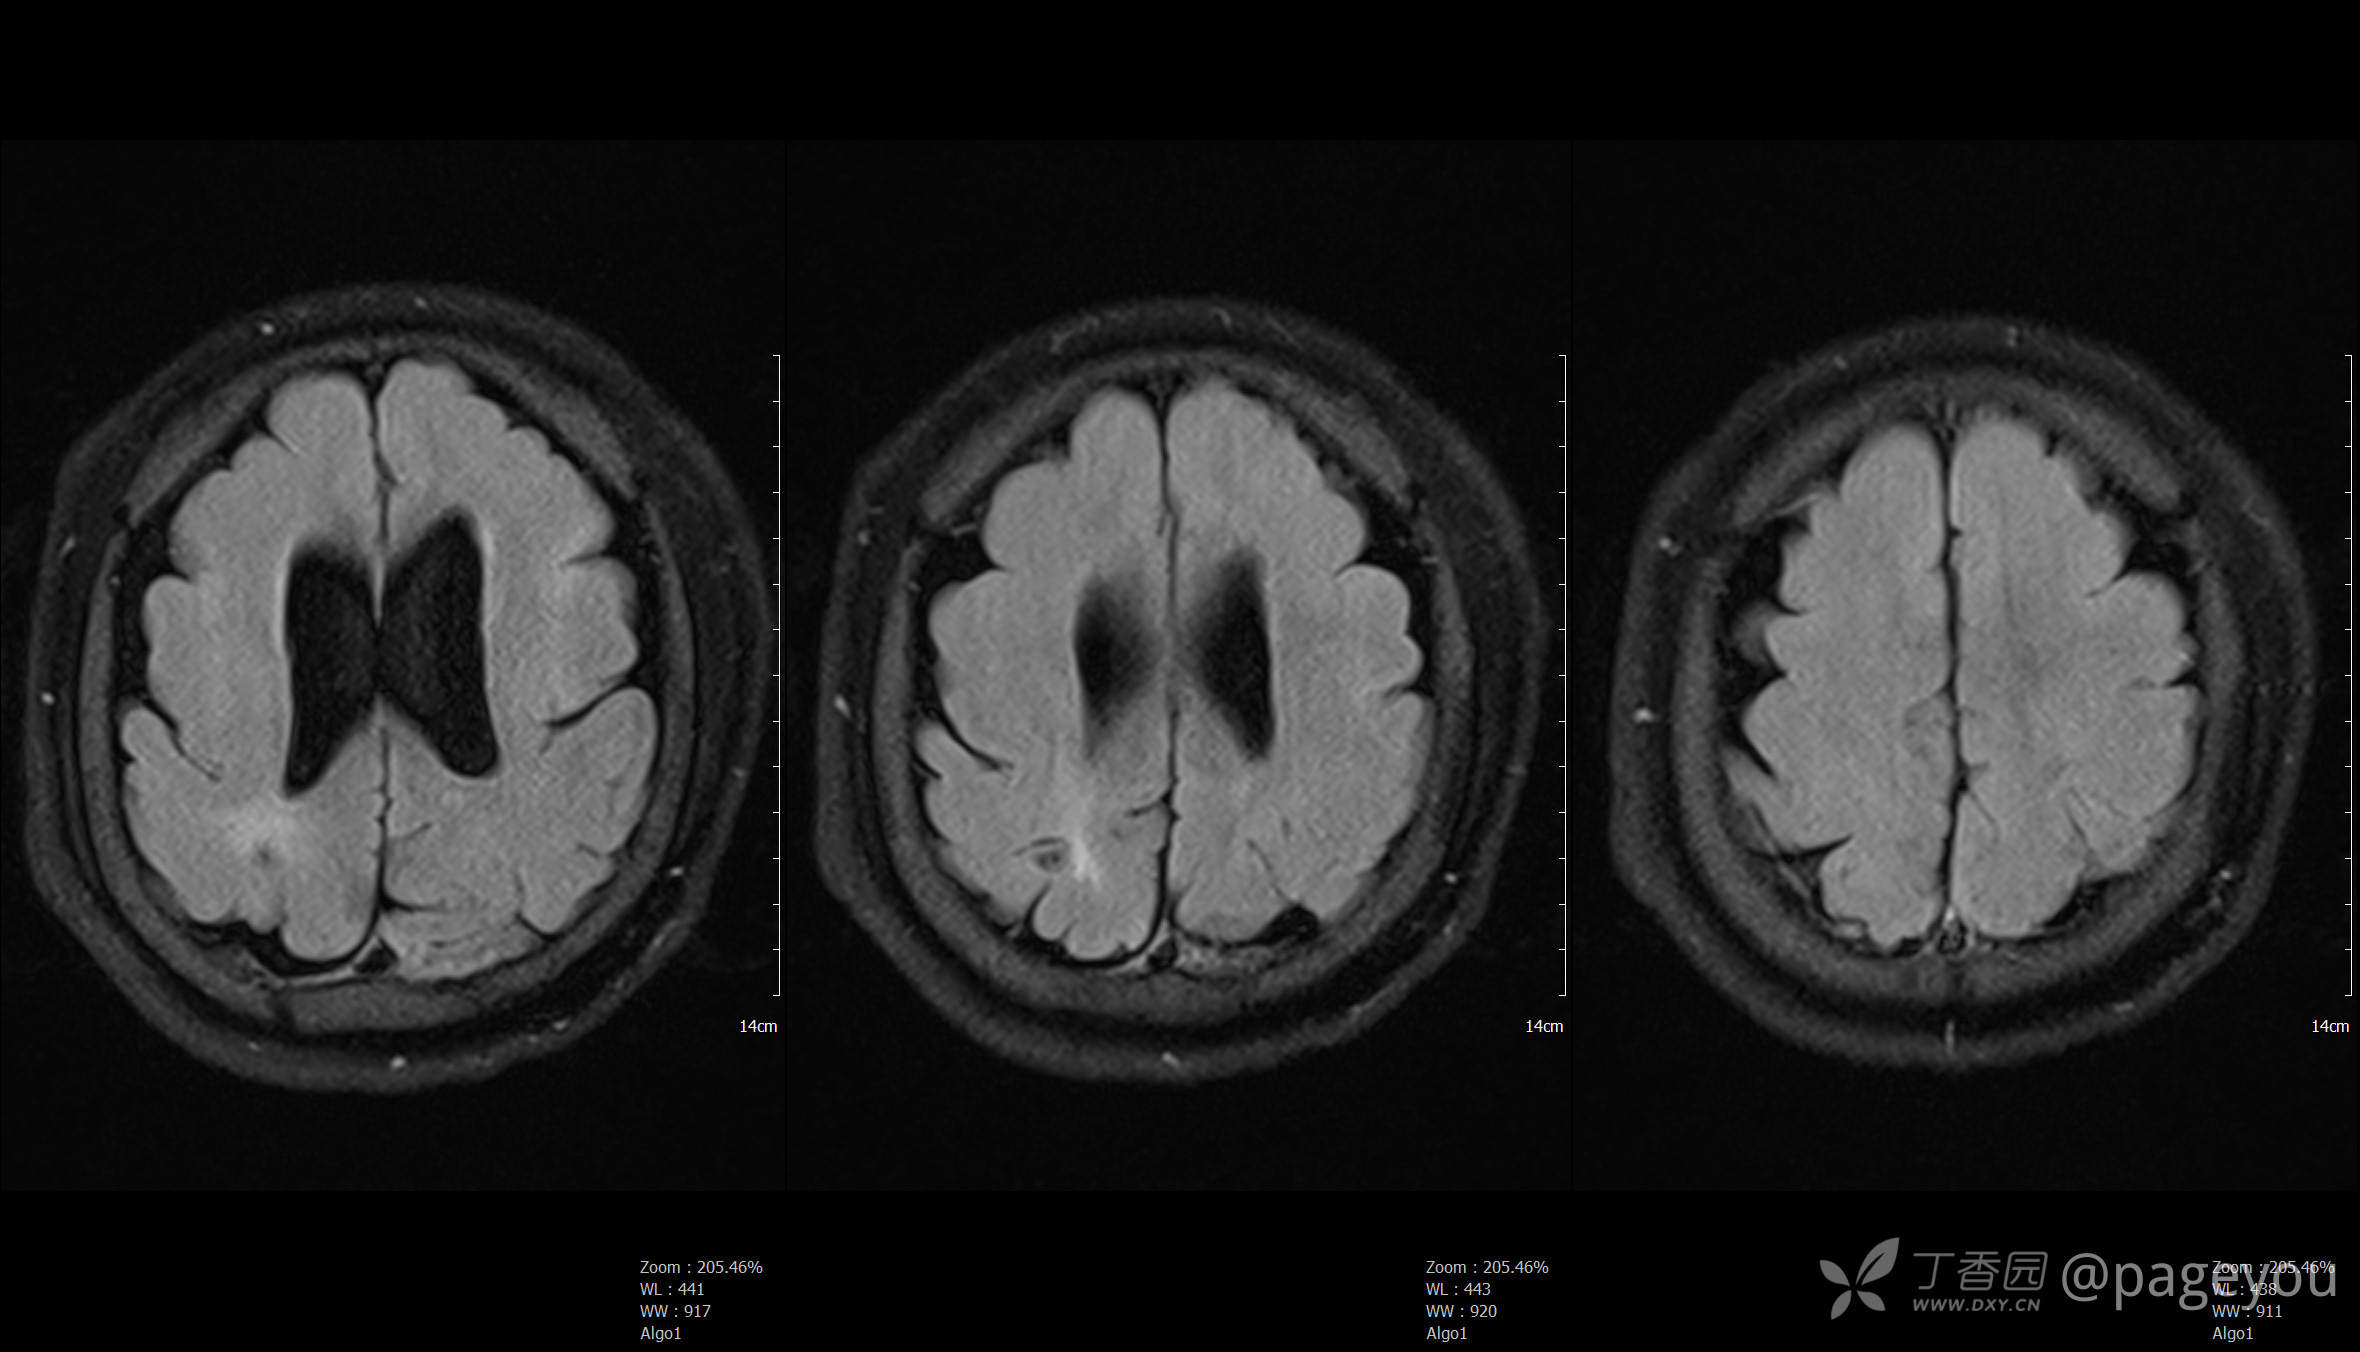

头颅MRI: